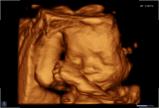

Seit März 2019 steht ein neues 3D/4D-Ultraschallgerät für faszinierende Eindrücke von Ihrem Baby zur Verfügung.

Außer den Fotos können auch 3D/4D Viedeoclips gemacht und auf einem USB-Stick gespeichert werden. So können die Bilder und Clips jederzeit angesehen werden.